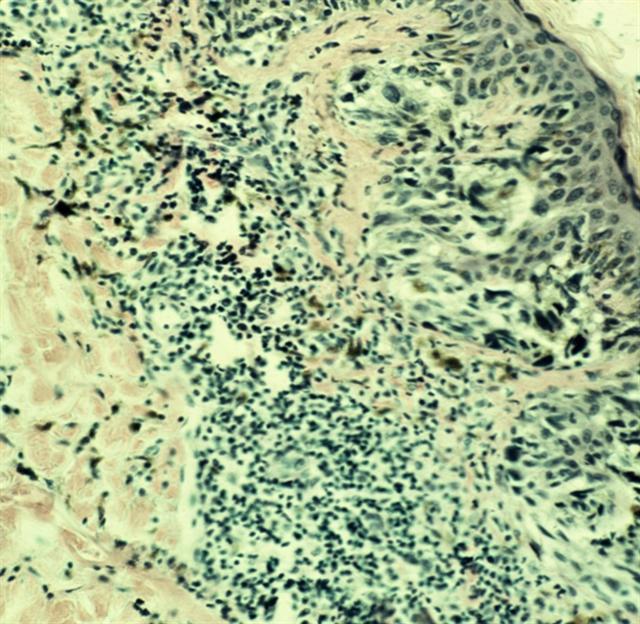

Рис. 2. Микропрепарат меланомы кожи: ячейки опухолевых клеток в сосочковом и сетчатом слоях дермы. Окраска гематоксилином и эозином; ´200.